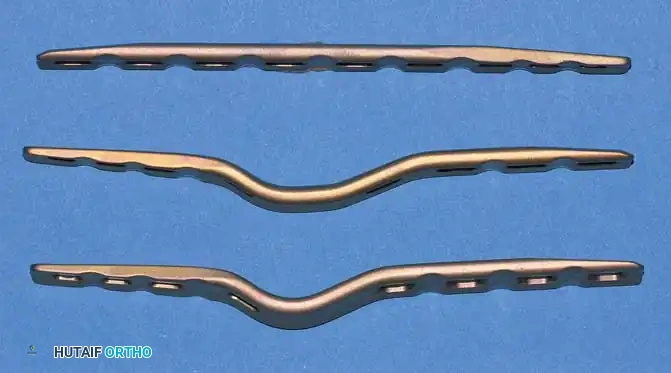

Fig. 4-19: Three types of AO wrist arthrodesis plates: straight plate, long carpal bend, and short carpal bend. All utilize three 2.7-mm metacarpal screws, one 2.7-mm capitate screw, and four 3.5-mm radius screws.

- Straight Plate: Employed when a large intercalary structural graft is required (e.g., post-tumor resection or massive traumatic bone loss).

- Short Carpal Bend: Utilized in smaller wrists or when the proximal carpal row has been previously resected (e.g., Proximal Row Carpectomy).

- Long Carpal Bend: The standard choice for large wrists with intact carpal rows.

These plates feature tapered edges and recessed screw holes to minimize dorsal soft-tissue irritation. Despite this low-profile design, the lack of dorsal subcutaneous fat means hardware removal is still required in approximately 15% of cases due to symptomatic prominence. Biomechanical studies by Morelli et al. confirmed that while DCP fixation is vastly superior to Steinmann pins, there is no significant biomechanical difference in stability between a standard 3.5-mm DCP and the precontoured low-profile plates. If a standard 3.5-mm reconstruction or DCP is used, it must be meticulously contoured intraoperatively to match the dorsal wrist anatomy.